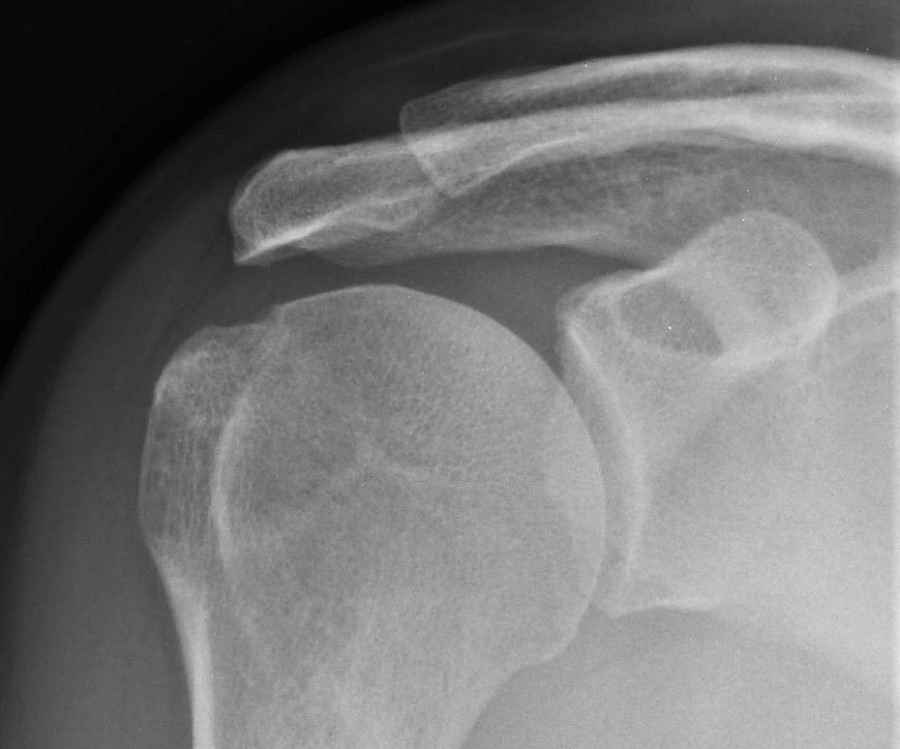

Acromioclavicular Joint

The acromioclavicular joint is the articulation between the end of the collar bone and the shoulder blade.  It is the joint most commonly affected by arthritis, but may also become displaced after injury.